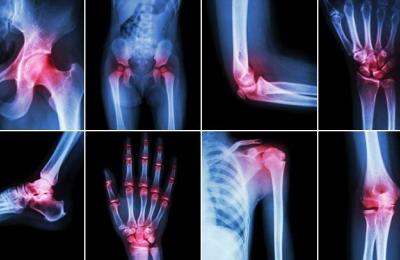

02.06.2020 Свикнали сме да възприемаме болките в ставите като следствие от прекомерно физическо натоварване, травми или стареенето на организма. Оказва се обаче, че редица болести са пряко или косвено свързани... |

11.02.2019 Обезводняването може да доведе до засилване на болката в ставите, засегнати от остеоартроза, ревматоиден артрит, подагра и други заболявания свързани с тях.

При недостатъчна хидратация можем да... |

19.10.2018 Остеопорозата е заболяване, което се характеризира с намаляване на масата на костното вещество и влошаване на структурата на костната тъкан, които водят до повишена костна чупливост и увеличаване на... |